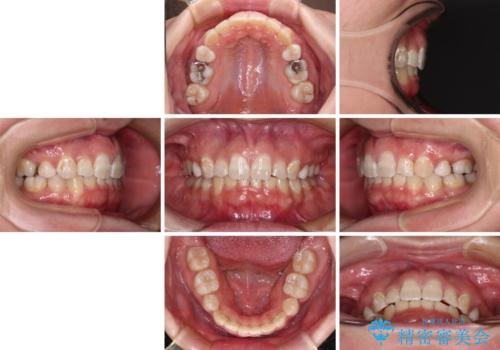

著しい八重歯を短期間で改善 ワイヤー装置による抜歯矯正

- 20代女性

- 審美装置

下顎小臼歯の欠損により過蓋咬合となっていたため、下顎は臼歯を起こすことで咬み合わせを改善し、八重歯は第一小臼歯2本を抜歯し、補助装置を使用して速やかに改善することとしました。

著しい過蓋咬合の改善が必要であった割には、治療期間は2年強と標準的でした。

八重歯は3,4か月で速やかに改善されました。